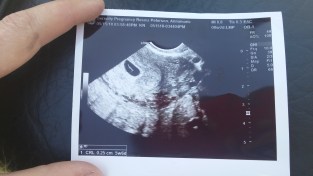

- In May, we drove back to MN to see family for the first time since our move out West. While we were there, we were ecstatic to find out we were expecting again! Cue anxiety (ha, ha).

Tiny Baby P @ less than 6 weeks. - June brought with it absolutely GORGEOUS scenery and ranch life. Foals, calves, perfect weather, green for the first time! We spent time in the mountains getting fences ready to move the cattle up there for the summer. Rex and most of the boys entered the cow-riding event at the local rodeo, what a blast! My prize for video-taping was my beet red sunburn. A few boys went home to their families this month, which brought us new boys in their stead. Looking back, I’m so grateful, but let’s just say this: Thirteen is Not. My. Favorite. Age 😉

- August brought with it a heat wave of 100+ temps, and the sweetest visit from my grandma Brenda and grandpa Dave. We drove up into the Beartooth Mountains and went through the pass; and what do you know, it was snowing up there! It ended up being a longer drive than we thought, but we made it 🙂 Grandma and grandpa came with me to my prenatal the next morning, and were so pleased to see baby P moving around and getting so big. It was such a sweet moment to share!